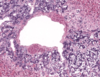

Pancreas